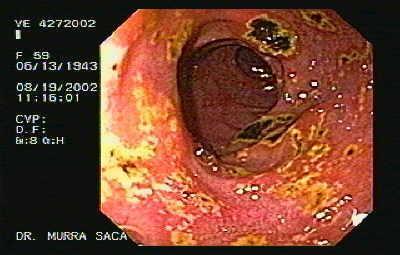

Características Anatomopatológicas: Al contrario que una úlcera duodenal, la úlcera gástrica puede ser maligna; las úlceras gástricas benignas son muy raras y tienen similitudes histológicas con las duodenales. La úlcera gástrica suele ser única, de forma redondeada u oval, siendo su diámetro generalmente < 3 cm.

úlcera gástrica